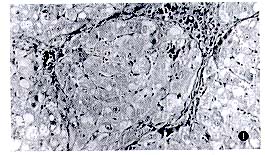

病理检查 模型组:正常的肝小叶结构被破坏,由广泛增生的纤维组织将肝

小叶分割包绕成大小不等的肝细胞团,形成假小叶,肝细胞肿胀,呈水变性,部分

肝细胞脂肪变性,可见肝细胞的点状坏死(图1). 肝炎平组:肝细胞的脂肪变性与

水变性明显减轻,纤维结缔组织明显减少,未见明显的假小叶形成(图2).

图1 模型组 肝小叶结构被破坏,纤维组织增生明显,假小叶形成 HE × 200

图2 肝炎平组 肝细胞肿胀,少量纤维组织增生,无假小叶形成 HE×200